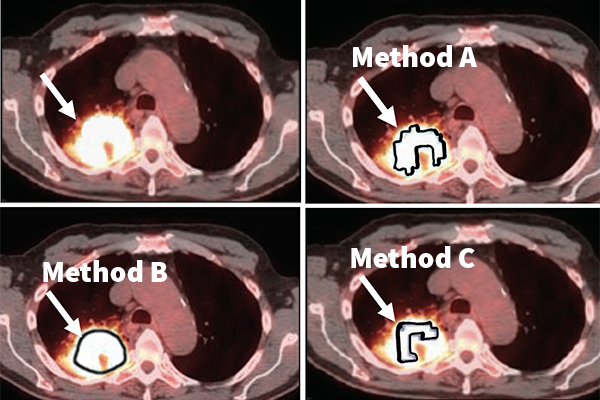

Which method to choose to delineate the tumor? In this example application, Jha’s task is to find the metabolic tumor volume from a clinical PET image (top left). The photos in the top right and bottom row show that different segmentation methods to measure this volume give different results, demonstrating the need for no-gold-standard evaluation to find the optimal method. (Jha lab)}

Jha, his collaborators and members of his Computational Medical Imaging lab will evaluate the efficacy of this no-gold-standard evaluation tool in evaluating different tumor segmentation methods on the task of measuring the volumetric features of metabolic tumor volume and total lesion glycolysis in images taken from patients with stage 3 non-small cell lung cancer.

“We will use this tool to identify the segmentation methods that yield the most reliable values for these volumetric features,” Jha said. “Our hypothesis is that the chosen segmentation method will provide a better prediction of whether a patient is responding or not early during the treatment. Accurate prediction of therapy response will help decide if the therapy must be continued or needs to be modified. Thus, this will help personalize therapy for the patient."